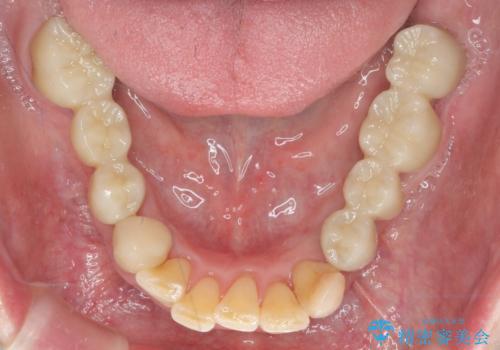

多発した虫歯による咬合崩壊 インプラントを用いた全顎治療

歯の破折・再発した大きな虫歯・根尖病変・歯の欠損、これらの問題を根管治療・歯周外科・インプラント治療・セラミック補綴を行うことで一つづつ解決し安定した咬合状となるよう治療を進めます。

口腔内全体を治療する全顎治療は、期間も長く外科を行う回数も多いためしっかりと通っていただくことが必要不可欠になります。

治療に加えて歯ブラシも上手になることが、治療した歯を長持ちさせるのに必要な要件となります。